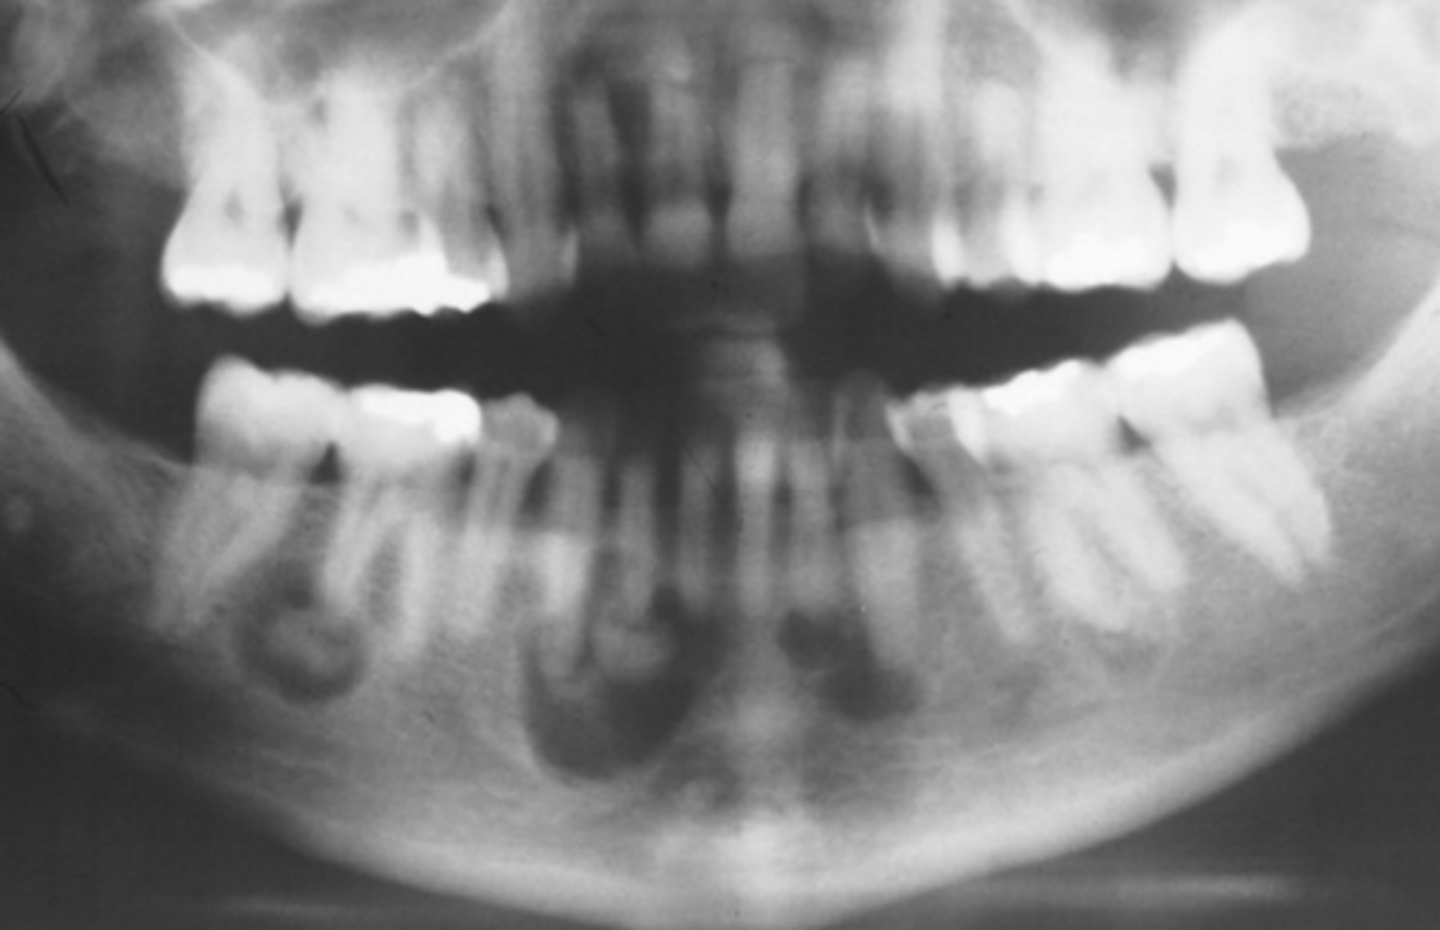

What area does odontogenic keratocyst (OKC) expand?

Mandibular posterior area

How does odontogenic keratocyst (OKC) expand around teeth?

Around entire tooth

What is the recurrence rate of odontogenic keratocyst (OKC)?

High recurrence rate

What are the differential diagnoses for odontogenic keratocyst (OKC)?

Ameloblastoma, dangerous cyst